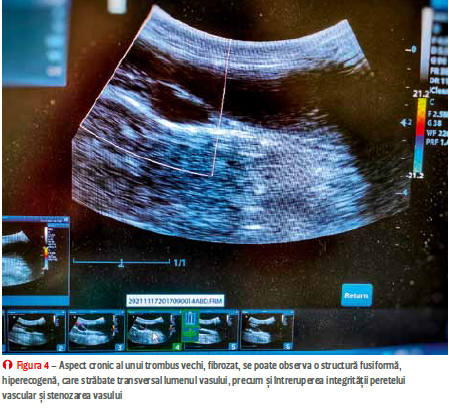

în lipsa lui, unele sonde cu frecvență înaltă pot pune în evidență fluxul laminar. Cazurile unde suspiciunea obliterării totale nu este confirmată ultrasonografic (fibrozări extensive, leziuni locale greu de pus în evidență) pot fi evaluate cu ajutorul ultrasonografiei cu substanță de contrast. Trombozele acute se rezolvă fie prin intermediul proceselor de fibrinoliză cu dizolvarea parțială sau totală a trombusului și recanalizare, sau prin fibrozarea acestuia și cu obstrucția vasului afectat (figura 4).